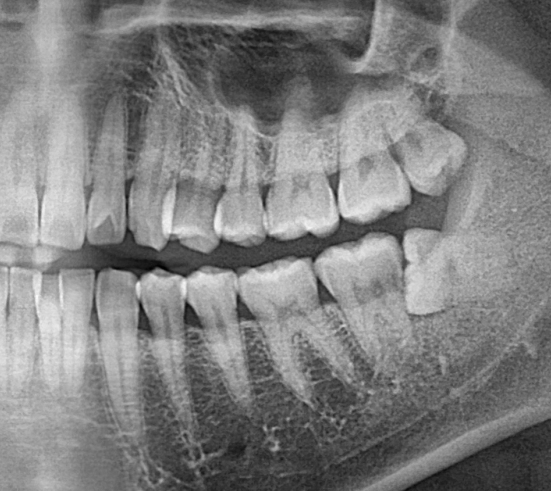

• 사랑니 발치 전

• 1번 째 사진

• 2번 째 사진

• 3번 째 사진

좌측 상악 사랑니는 발치가 안된거 같습니다. 이부분은 환불을 문의 하셔서 받으셔야될것같습니다 .

좌측 상악의 사랑니가 남아 있습니다 사랑니를 뽑지 않았다면 나중에 뽑아도 되기 때문에 치료를 받았던 치과에서 문의를 해 보는 것이 좋습니다

왼쪽 위 사랑니 (사진상 오른쪽 위) 는 그대로 남아있네요.

진료내역상 보면 위,아래 사랑니 발치가 2개를 한 것이 맞으므로 이는 문제가 될 수 있는 부분입니다.